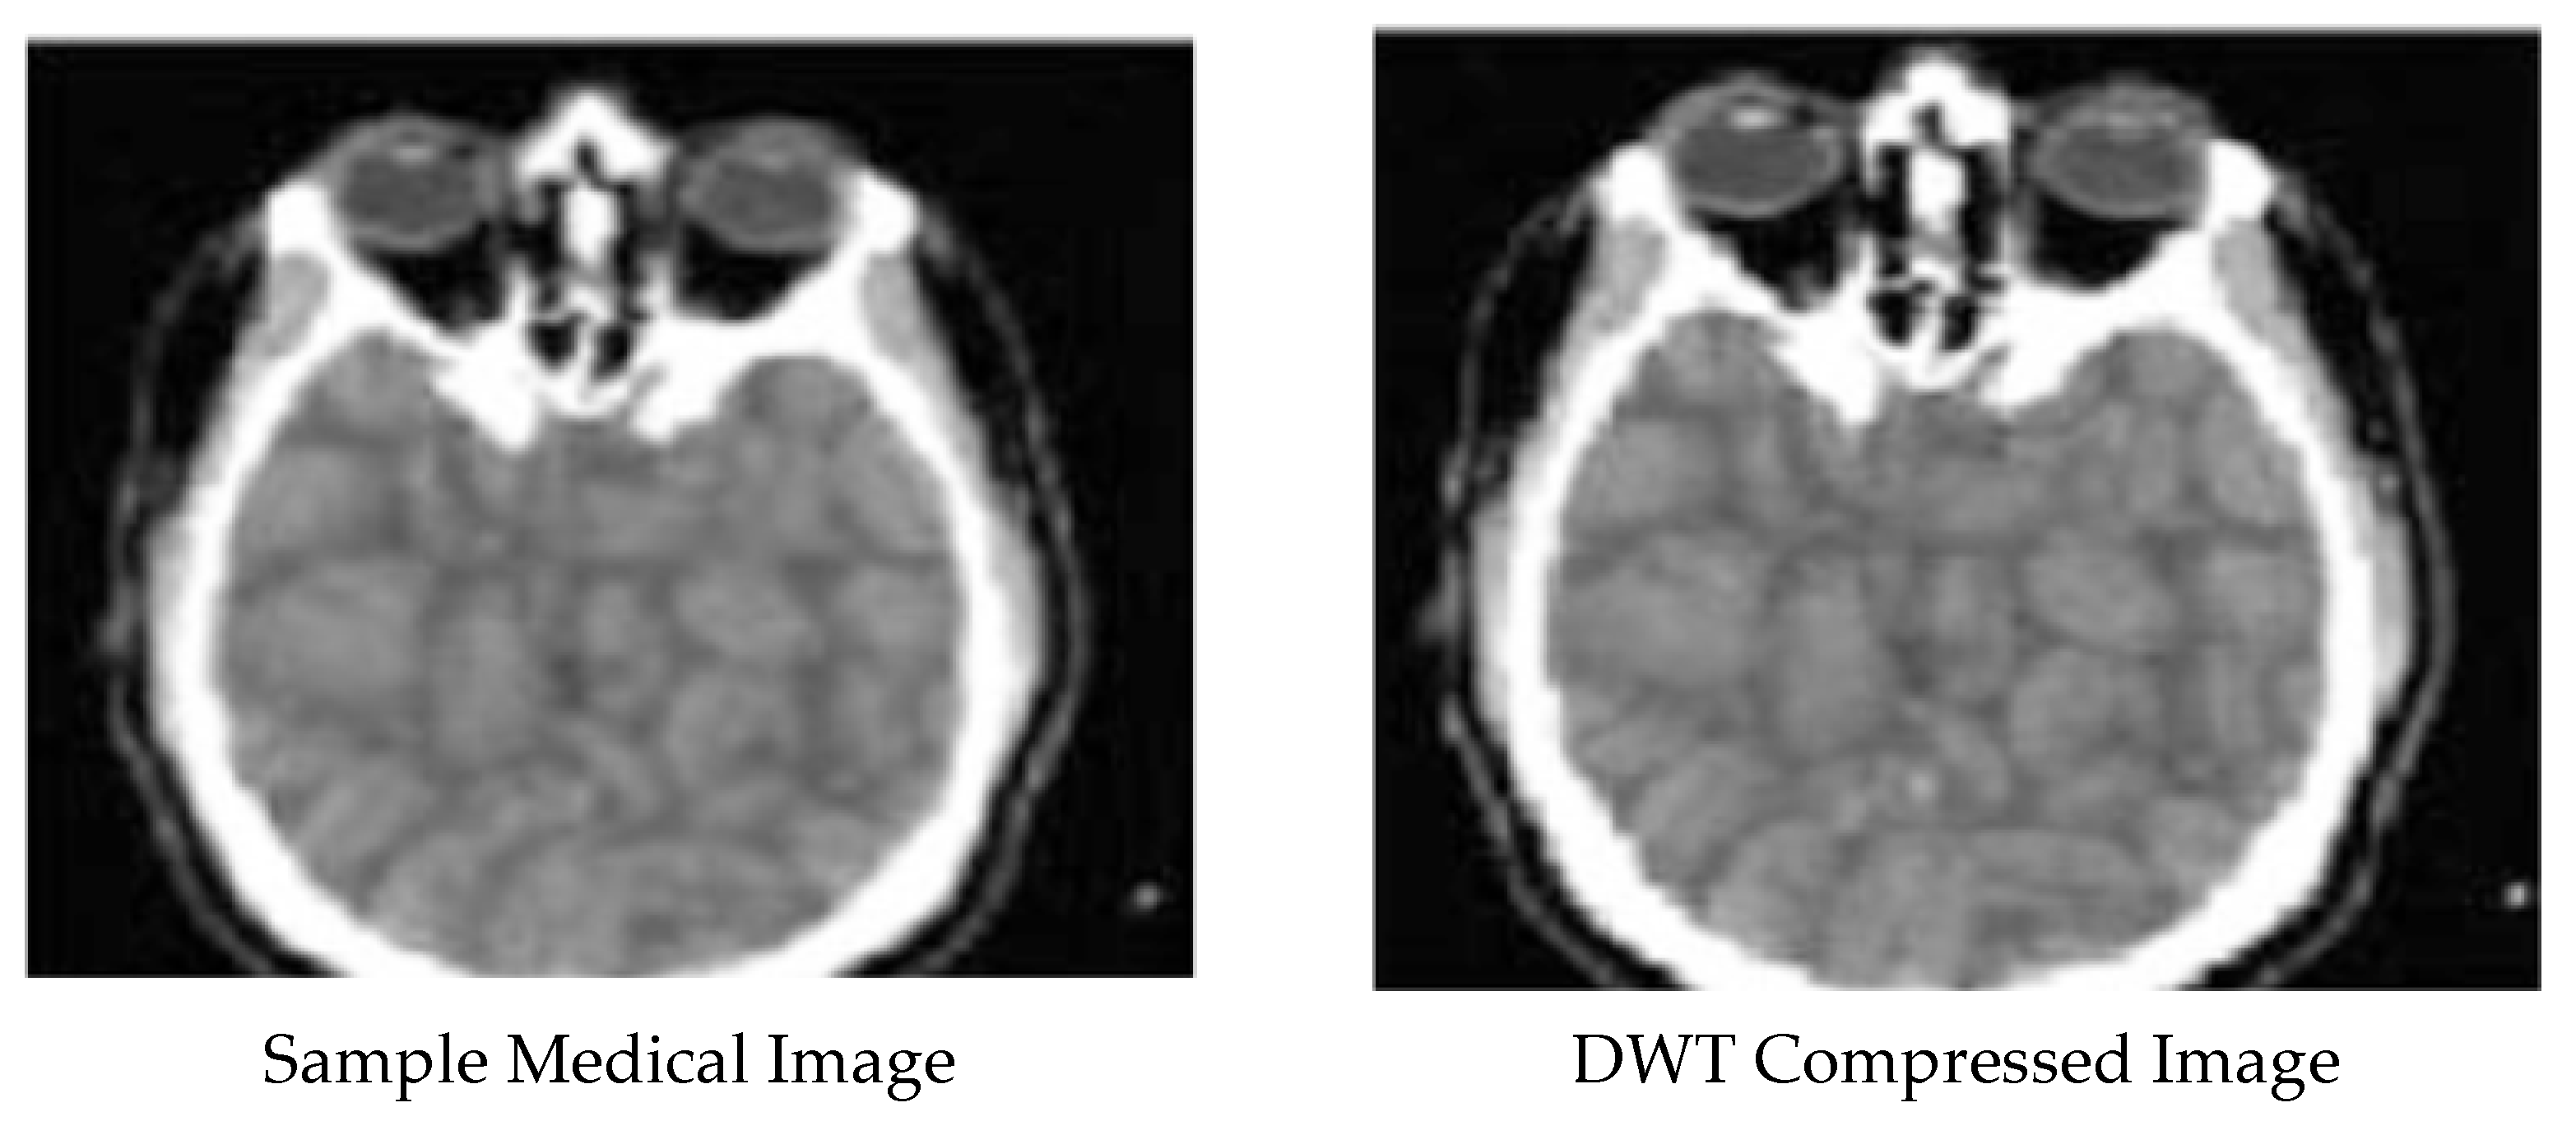

Enhanced and Compressed Output

5. Discussion

| 3 | DWT compressed image | 0.060732271 | 0.555070285 | 54.76541543 |

| 4 | AHE enhancement for DWT compressed image | 0.996540627 | 4.14 × 10−5 | 86.98046733 |

| 5 | MO enhancement for DWT compressed image | 0.919275875 | 0.012887986 | 72.76504215 |